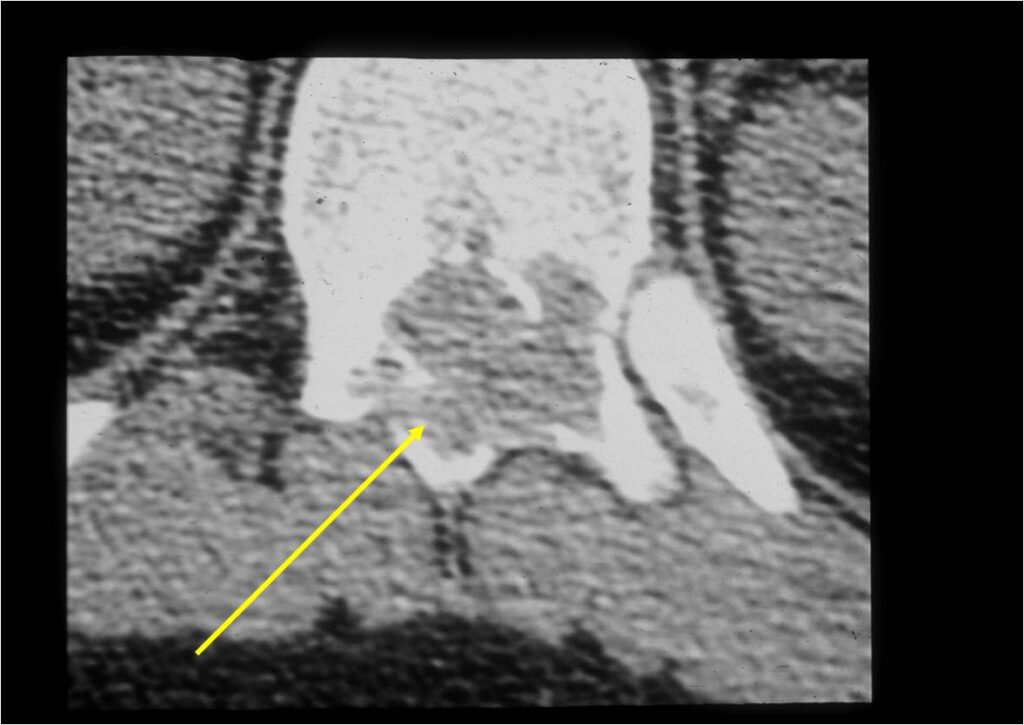

CT Scan:

- More useful for detecting mineralization and evaluating extent of bone destruction than plain X-ray

- The periosteum remains intact around the soft tissue component. Might need a CT scan to detect the subtle calcification (Egg Shell Rim of Calcification) associated with an intact periosteal reaction

- The lesion may be entirely radiolucent but usually shows some degree of mineralization. Mineralization may appear stippled like cartilage but do not see chondroid pathologically. Mineralization is sometimes better detected on a CT scan rather than an x-ray.